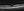

Factors influencing the likelihood of spontaneous resolution include a better presenting visual acuity, smaller vitreomacular attachment areas, and a V-shaped vitreous attachment (ie, a posterior hyaloid detached both nasally and temporally with respect to the fovea and attached only to the fovea; Figure).1

That said, patients with broad or J-shaped VMT (ie, vitreous cortex detached from the temporal retina but attached nasally to the fovea and to the fovea itself) that is associated with significant macular hole formation or epiretinal membrane may have a higher risk of poor anatomic and functional outcomes following surgery.1